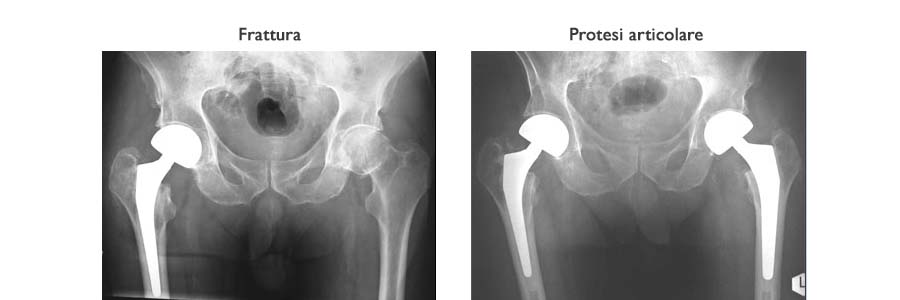

Le fratture del bacino sono eccezionali nel bambino, relativamente frequenti nell’anziano che soffre di osteoporosi. Nell’adulto giovane si tratta di fratture dopo un trauma molto violento e la gravità di queste lesioni dipende dallo spostamento dei frammenti e quindi dal coinvolgimento delle parti molli (vasi, arterie, vene, nervi).

Le fratture complesse del bacino sono traumi che mettono l’individuo in pericolo di vita e che richiedono assolutamente una valutazione chiara d’urgenza ed un trattamento immediato.